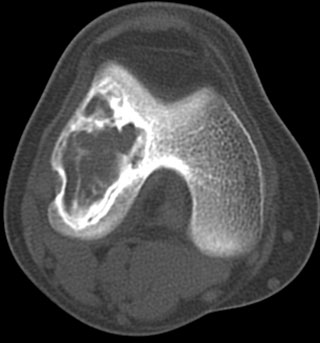

患者,女,32岁,因外伤后右膝疼痛而做ct检查.请大家讨论.有手术病检结果

股骨下端跨越骨骺、干骺端破坏性病变,内上方见多数斑片状钙化,并可见宽窄不一房隔,边缘硬化,无明显膨胀,关节面皮质连续,软组织内无肿块及钙化影。

考虑:软骨粘液样纤维瘤可能性大。

股骨下端跨越骨骺、干骺端破坏性病变,内上方见多数斑片状钙化或骨化,并可见宽窄不一房隔,边缘硬化,无明显膨胀,关节面皮质连续,无骨膜反应,软组织内无肿块及钙化影。

考虑:骨良性肿瘤病变----1成骨细胞瘤。2成软骨细胞瘤。3软骨粘液样纤维瘤。